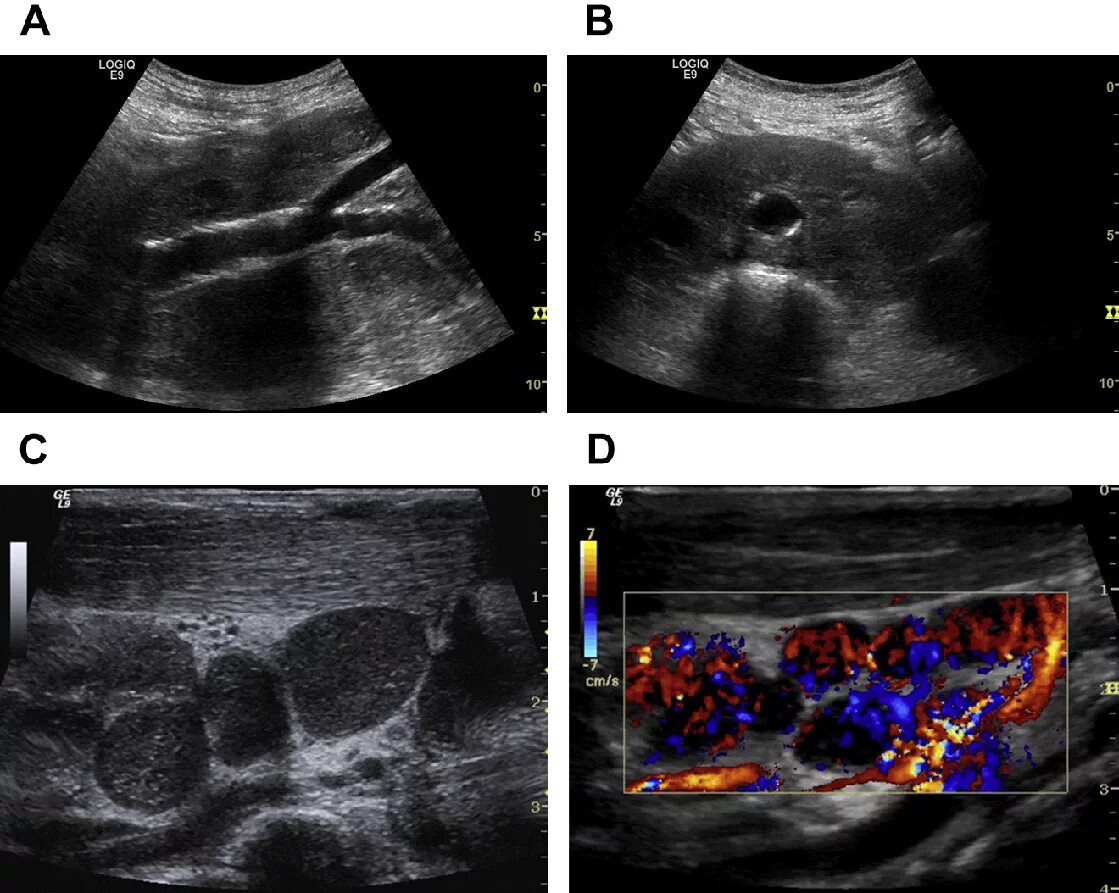

Метастазы в паховых лимфоузлах